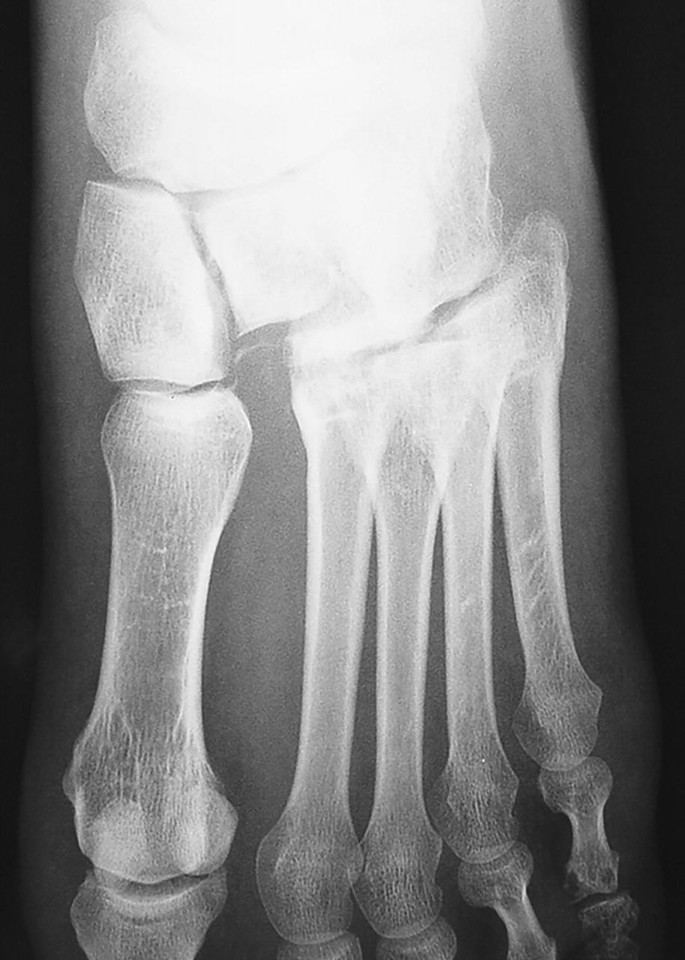

Foot and Ankle Dislocations SpringerLink What Is The Bone On Your Ankle Called  The inner bone is the tibia, or shinbone, which. What are the bones that make up the ankle, what are they called, their basic anatomy & structure, with pictures The top of the talus fits inside a socket that is formed by the lower end of the tibia (shinbone) and the fibula (the small bone of the lower leg). The. What Is The Bone On Your Ankle Called.

Ankle Anatomy Sprain, Clinical Anatomy, Fracture, Radiology, XRay What Is The Bone On Your Ankle Called  The ankle joint, also known as the talocrural joint, allows dorsiflexion and plantar flexion of the foot. The ankle joint, also known as the talocrural joint, is a synovial joint that connects the bones of the leg, the fibula and tibia, with the talus of the foot. Talus, calcaneus, navicular, cuboid, cuneiform. The 7 bones in the ankle are: The. What Is The Bone On Your Ankle Called.